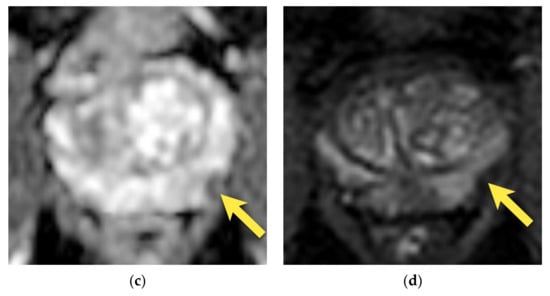

9. Prostatitis